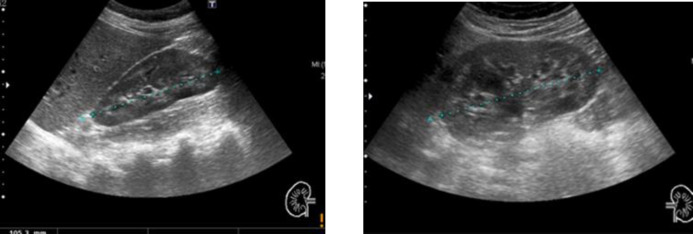

Background: Furosemide is a drug widely used for several medical conditions and could be used without medical prescription. Furosemide-related nephrocalcinosis can occur regardless of age, although the risk is higher in premature infants. The defining characteristic of nephrocalcinosis is generalized calcium deposition in the kidney. The most useful imaging studies for evaluation are ultrasonography and computed tomography (more effective in detecting calcification).

Case presentation: A 32-year-old woman with a history of depressive syndrome was admitted for evaluation of fortuitously discovered nephrocalcinosis and hypokalemia. The studies performed revealed the presence of a metabolic alkalosis with discrete hyperreninism/hyperaldosteronism but normal ratio, normotension and urinary study showed elevated sodium, chloride, potassium and calcium fluctuating in different determinations. Surreptitious diuretic intake was suspected and urine analysis revealed doses equivalent to 80-120 mg. The patient was advised to discontinue all diuretic treatment; she was adequately supplemented with potassium and she was followed-up in outpatient clinics. During the follow-up, clinical and analytical improvement was noted, which led to the discontinuation of supplementation.